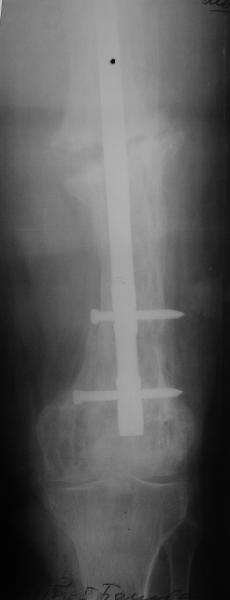

Еще один пример. Пациентка с юга России, прислала рентгенограммы через год. На сегодня прошло 2 г. 8 мес. после операции. Несмотря на не очень убедительный процесс сращения, пациентка ходит. Учитывая остеопороз при Педжете, решили, что динамизировать вообще не нужно.